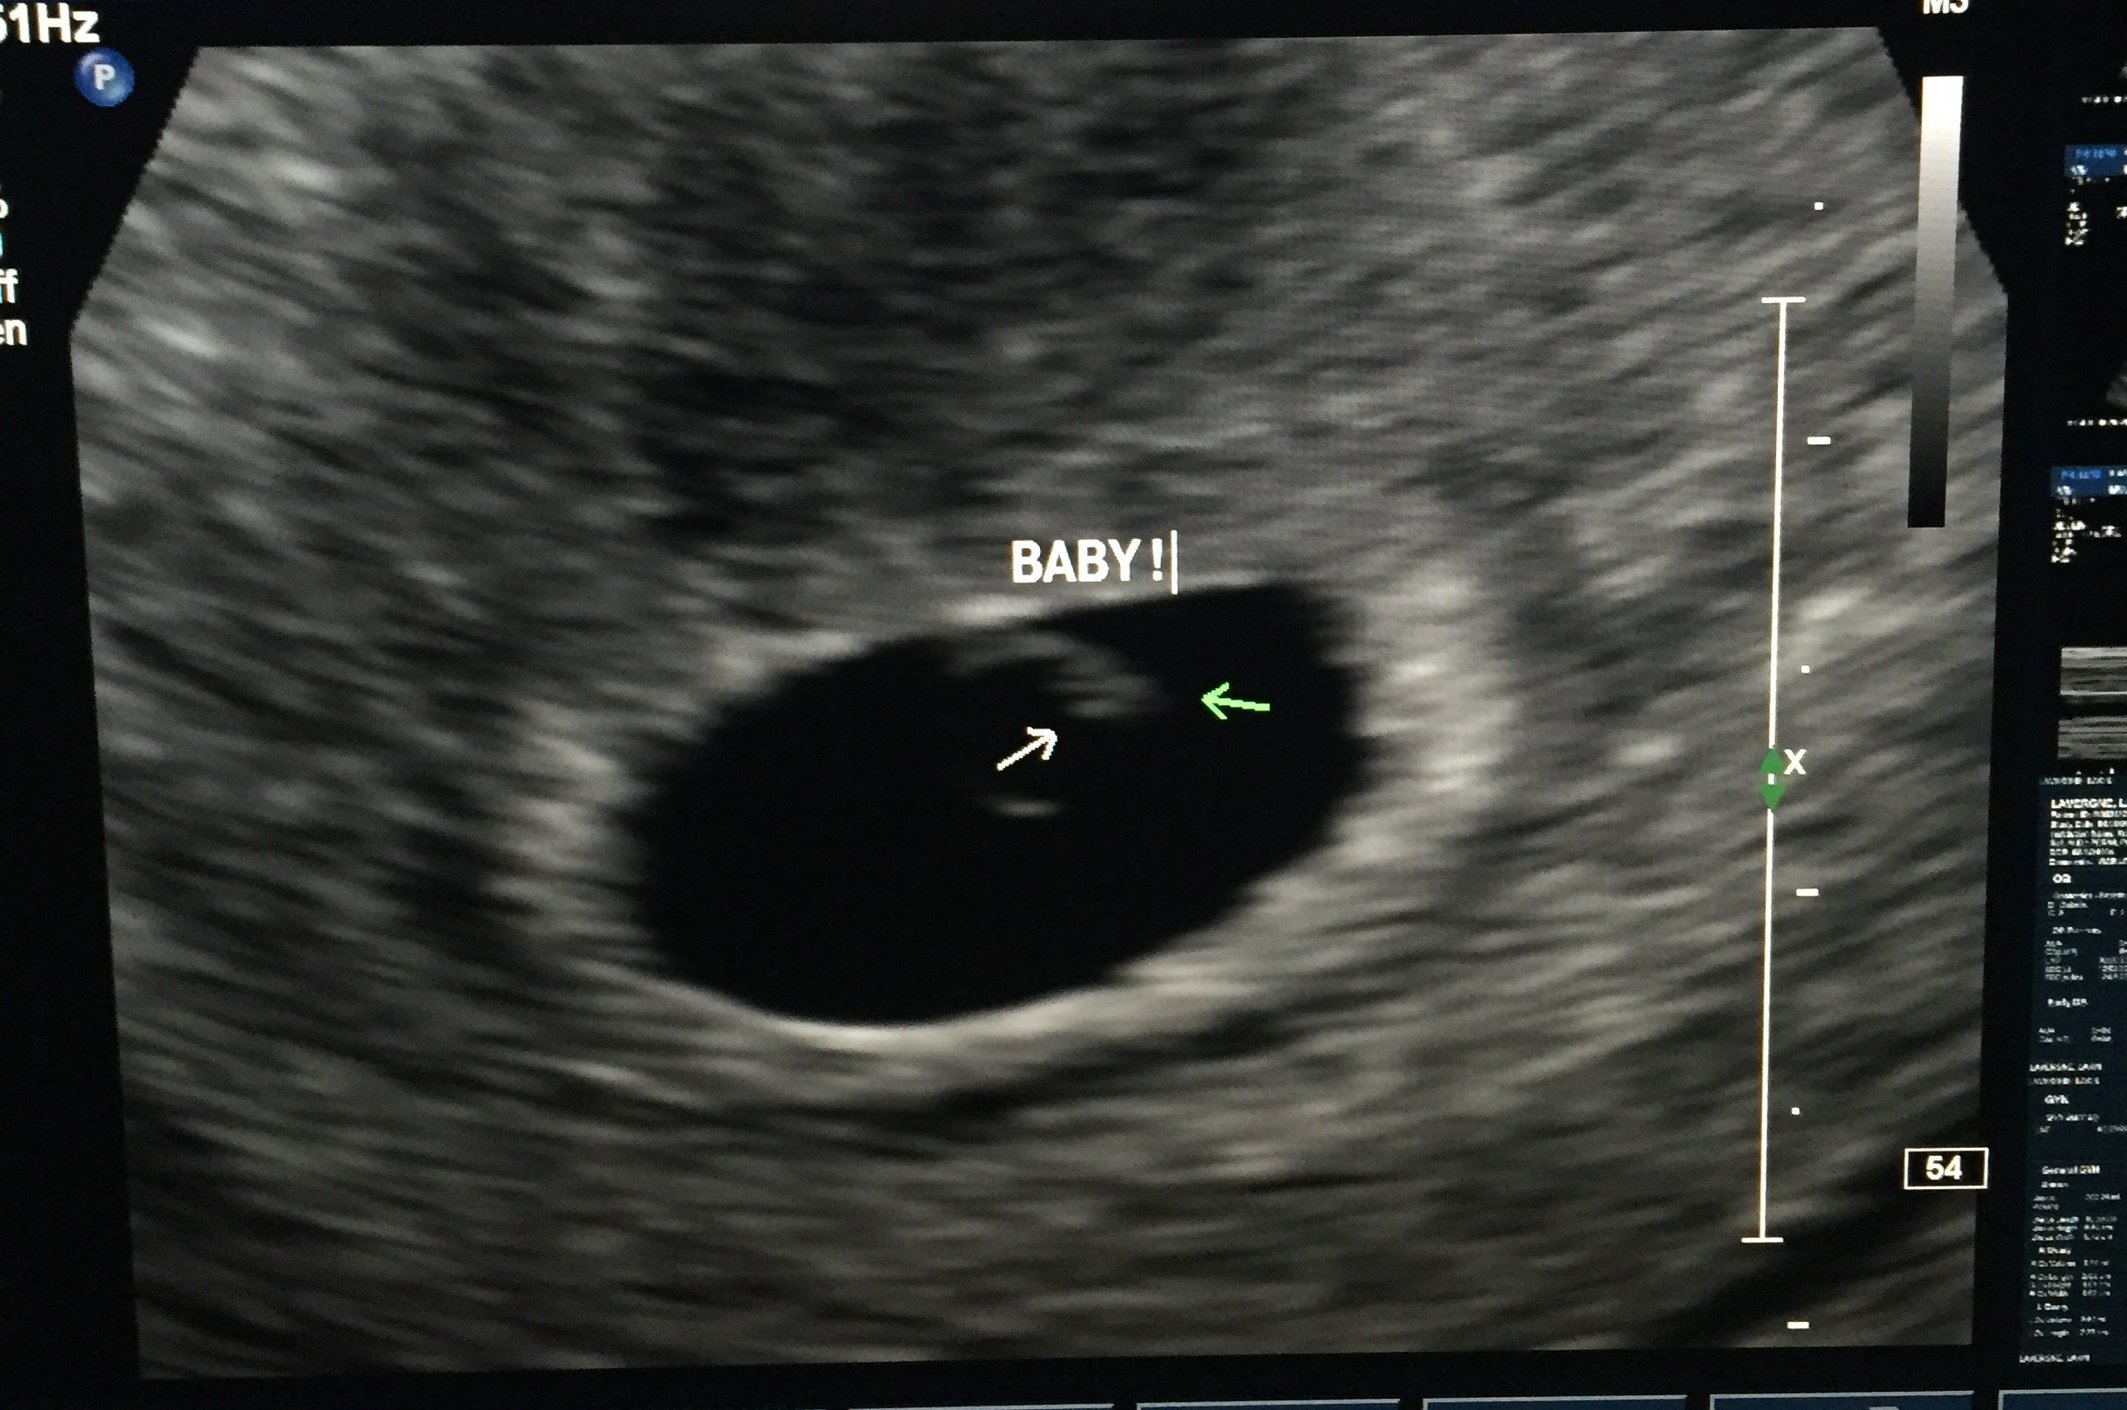

Had another check today at the RE. Left with a picture of a definite IUP with yolk sac & maybe more inside. Couldn't find heartbeat yet but the RE was happy with everything today. I go back next week.

It looks super tiny but you can definitely see stuff in the sac!

I didn't want to start an US thread (though I think we should have one) for fear of jinxing myself! But I will share with you ladies Sorry it is sideways!!